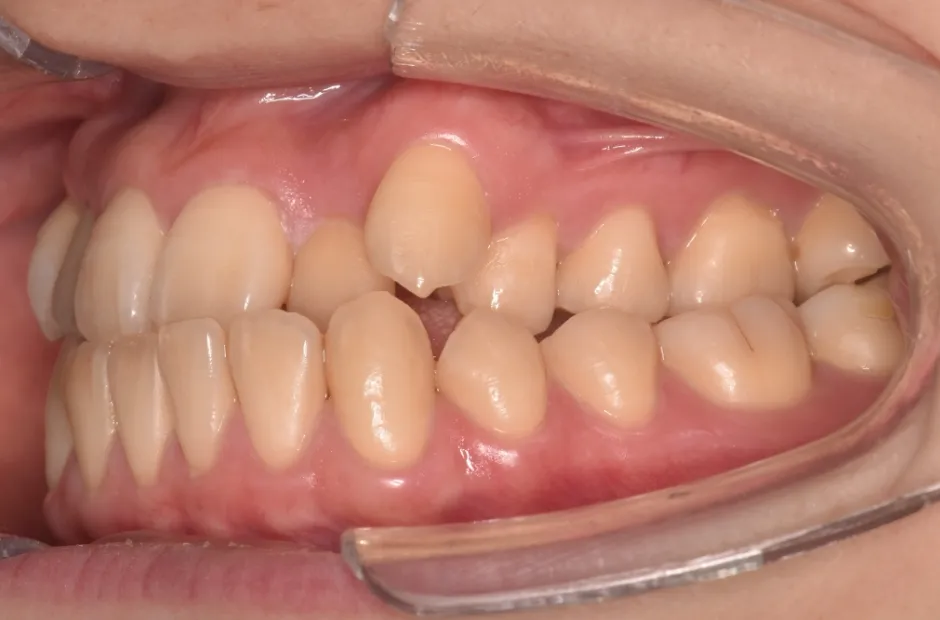

叢生

| 診断名・主訴 | 叢生 |

|---|---|

| 年齢・性別 | 43歳・女性 |

| 治療期間・回数 | 2年7か月 27回 |

| 治療に用いた主な装置 | 舌側矯正 |

| 抜歯部位 | 両顎4,4 |

| 治療費 | 100万円(税抜) |

| リスク・副作用 | 装置による違和感・疼痛・歯肉退縮・歯根吸収・虫歯のリスクなど |

治療前